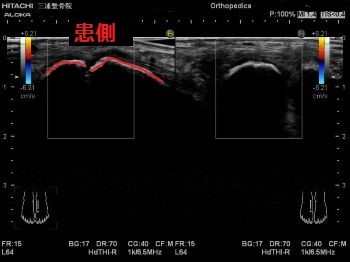

エコーではこのように写ります。

患側では大きく腫れて

正常な靭帯線維が見えないため

二分靭帯が断裂しています。

エコーの良い所として

動かしながらも観れるので

関節がどのくらいぐらついているかなども

判断できます。